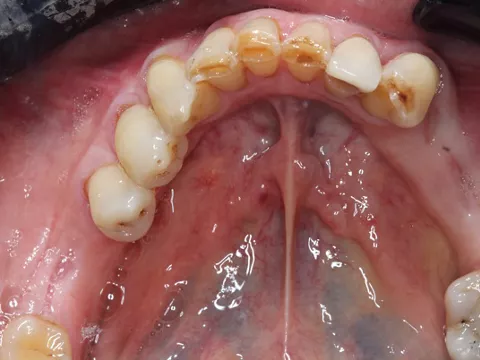

Initial situation

2a. 2b. Preoperative frontal and occlusal view of the lower arch showing multiple missing teeth.

2a

2b